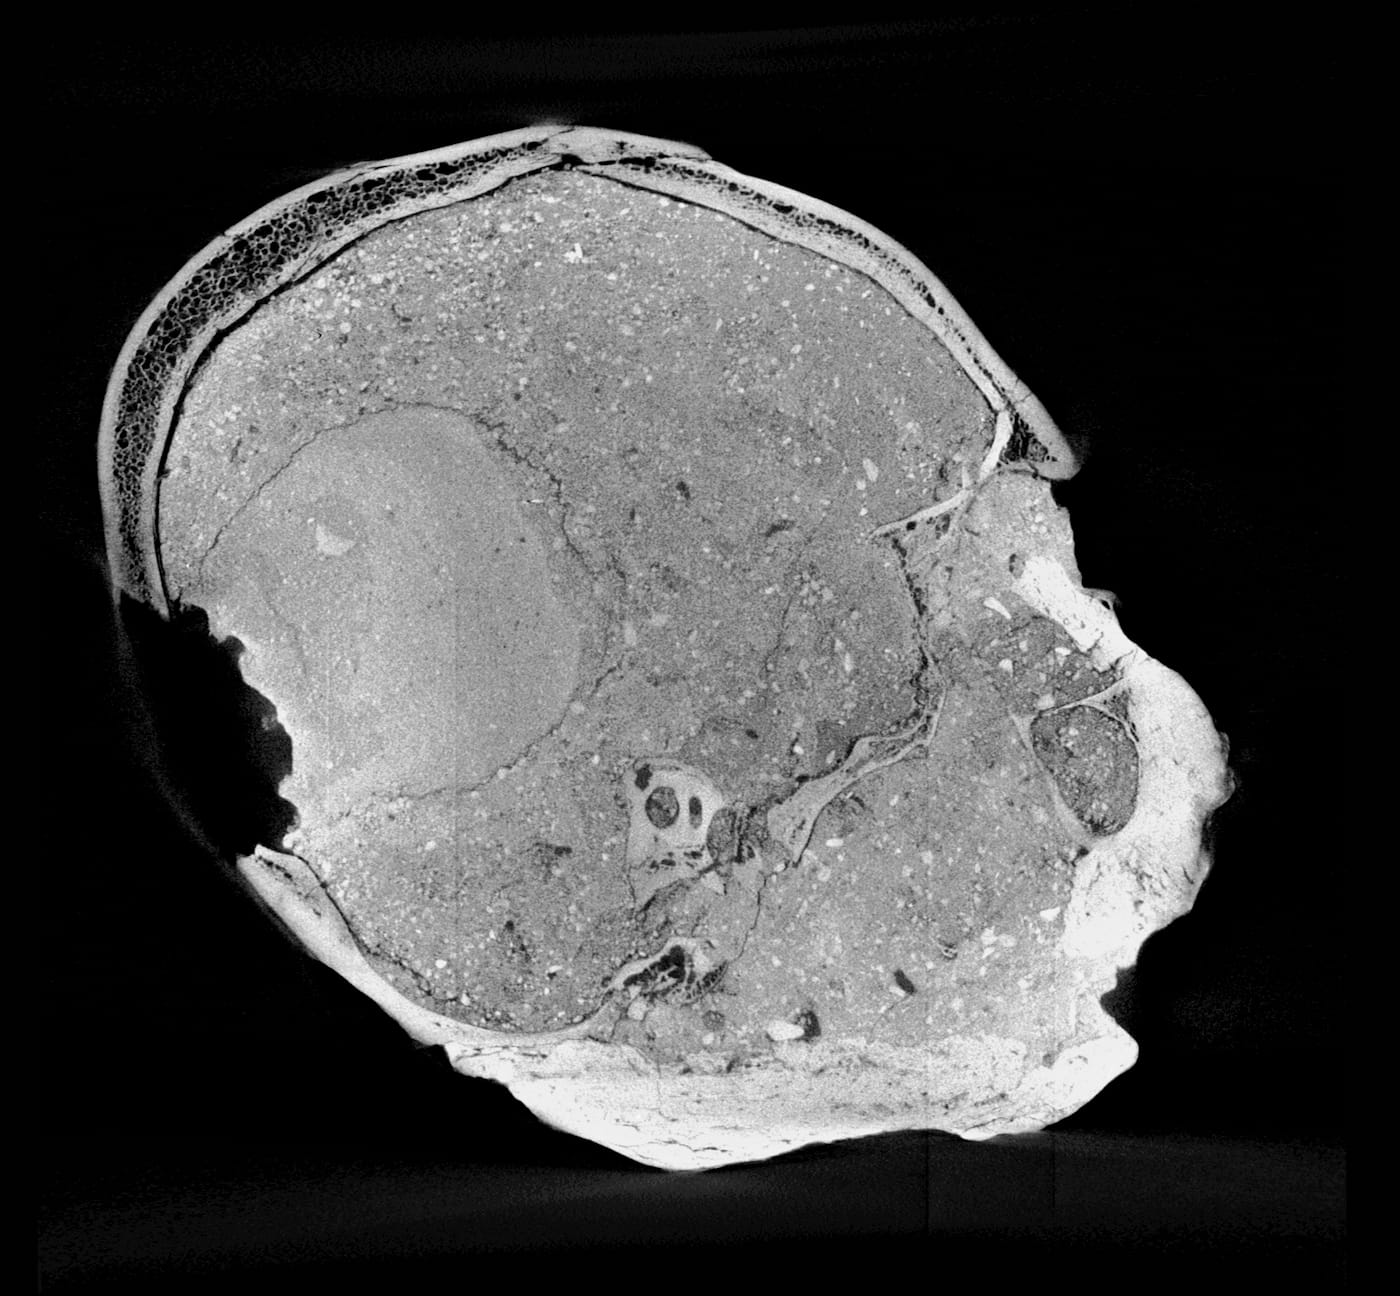

The oldest portrait in the British Museum’s collection is neither a painting nor a bust — it’s a 9,500-year-old human skull, decorated with plaster. Known as the Jericho Skull, it is one of seven plastered ones archaeologists found in 1953 in the ancient settlement near the Jordan River, now all scattered in institutional collections around the world. Besides the plaster layer modeled over the bone, marine shells fill its sockets and soil fills its interior for support, transforming what would have been strict cartilaginous remains into an artful commemoration of the deceased.

We now have an idea of what this particular individual looked like, as experts at the Natural History Museum’s Imaging and Analysis Center have used micro-CT scanning to create a 3D facial reconstruction of the Jericho Skull. The head, which is currently on display, depicts a man in at least his 40s who likely underwent ritual skull reshaping when he was younger, as suggested by the slight broadening of his head across the back.

The plastered face may have initially been made to commemorate this specific, anonymous man, but it may have grown over time to be regarded as an ancestor figure to unite a community, Fletcher said. Such a role would have been significant, helping to overcome any social tension that may arise from the conditions of living in large numbers. Surface wear and extensive fractures in the plaster face — present, too, in the six other crania — support this theory, suggesting that it was handled frequently, possibly over hundreds of years.

The imaging team conducted its own sculptural process, but one, of course, aided with the latest digital technologies. Experts first digitally separated the shape of the skull bones from the overlying plaster then converted data from a micro-CT scan to create a 3D-printed model of the cranium. As the mandible was not present, the team added a lower jaw constructed based on data from other known examples of human mandibles of similar age and geographic origin. The face was then built over the skull model — this time, in a more traditional sculptural process: experts used clay and wax to build features from the bone-up, muscle by muscle, creating every anatomical detail before topping it off with a clay layer of tissue and skin. Finally, they made a mold of the head from which the displayed face was cast in Jesmonite — essentially a mixture of gypsum and acrylic resin.